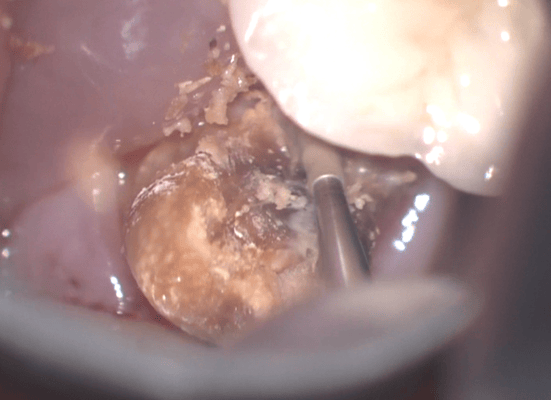

クラウンを外すと、歯肉縁下までの大きな虫歯が確認できます。ラバーダムができないので、簡易防湿を行い、歯肉溝からの浸出液の侵入を防ぎます。隣の歯の間にまたがる虫歯ですが、丁寧に軟化象牙質を除去します。歯髄の露出はありましたが、特殊なセメントで緊密にシール(絆創膏みたいなもの)します。歯髄を除去せずにすみました。